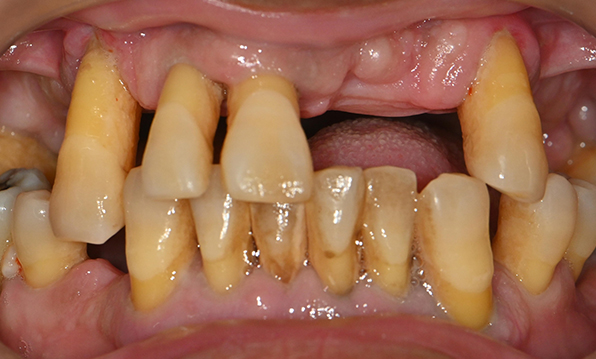

Before & After

| Before | After |